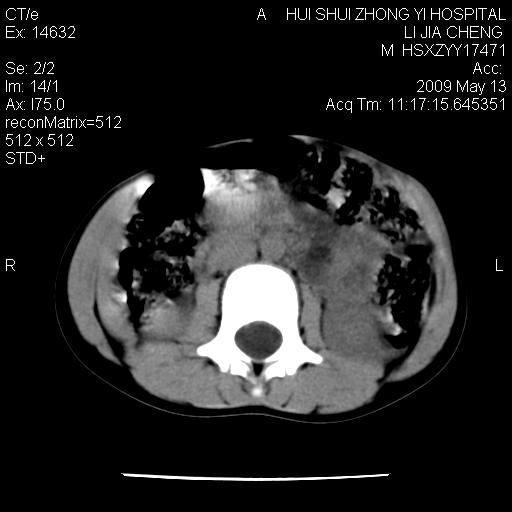

标题: PED1887:男性,6岁。反复脐周疼痛2年余。请各位老师看下腹 [打印本页]

标题: PED1887:男性,6岁。反复脐周疼痛2年余。请各位老师看下腹

该患者可自行好转,大小便未见异常,化验:便未见虫卵,血常规:wbc:8000;淋巴3600,中性45%

肠道准备不足,im15---------------------18左侧腹腔病变?

来源于十二指肠水平部病变?建议行进一步检查。

考虑腹疝可能。

是小肠,壁稍厚可能是肠腔未很好充盈所致,腹部ct扫描未见明显异常。